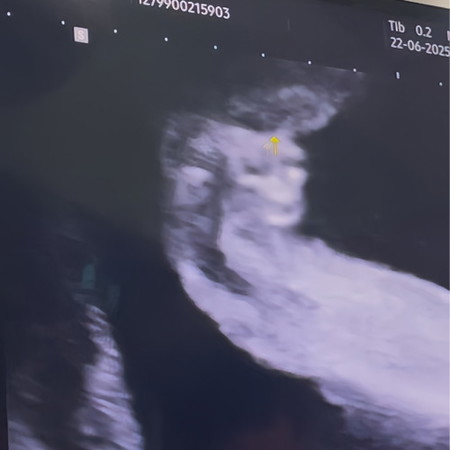

ภาพอัลตร้าซาวด์เพศ 20 วีค

ลูกสาว100%ไหมคะแม่ๆ🤣

ผู้หญิงนะคะ เป็นกลีบ

กลีบชัดเลยน๊าา🥰